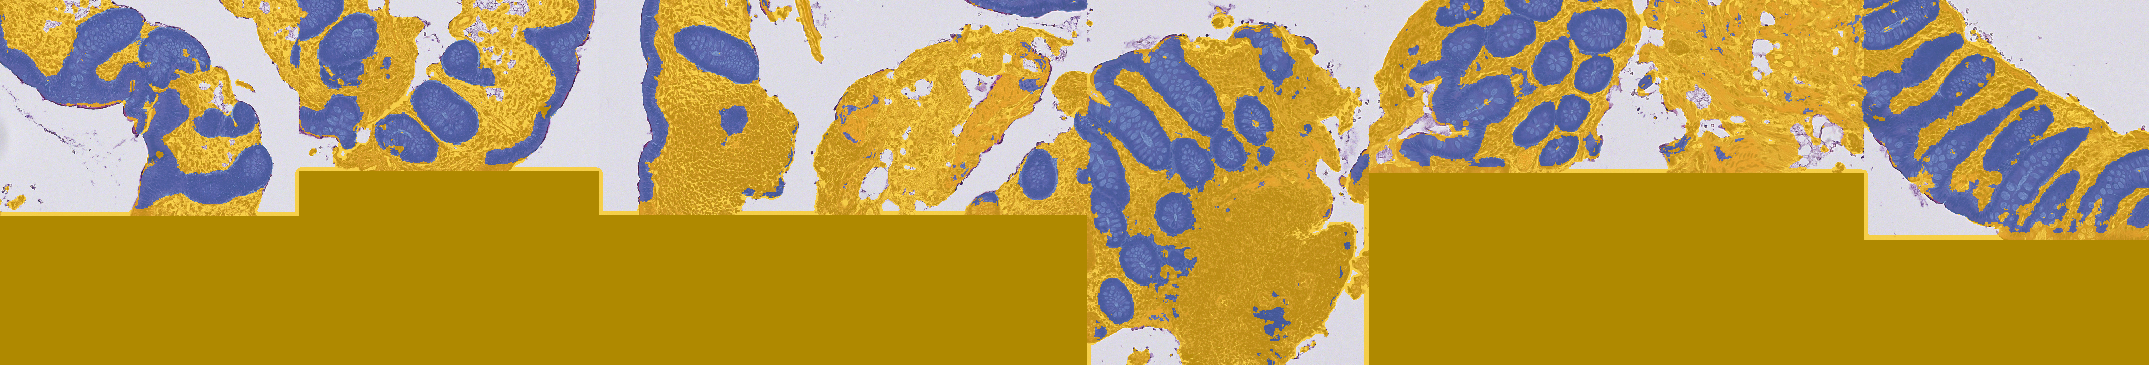

| Original image | Empty / chaotic | Interesting |

|---|---|---|

![]() |